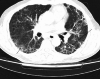

The new disease caused by severe acute respiratory syndrome coronavirus 2 (SARS-CoV-2) was dubbed coronavirus disease 2019 (COVID-19) by the World Health Organization and declared a pandemic. Initially thought to be a pathogen that primarily attacks the lungs, SARS-CoV-2 has turned out to be a much more formidable foe impacting almost every organ and system aggressively. I report the case of a 60-year-old man who came to the ED due to symptoms of high fever, headache, mild confusion, dry cough and exacerbated dyspnea since the last 24 hours. He had a history of idiopathic pulmonary fibrosis (IPF) and was undergoing treatment with antifibrotic medication. Apart from IPF, he had no other comorbid. He acquired SARS-CoV-2 infection by close contact and infection deteriorated into pneumonia and septic shock. Complete blood count showed white blood cells at 3.3×103/μL and platelets at 71×103/μL; lymphocyte count was low. Arterial blood gases revealed metabolic acidosis. Definitive diagnosis was by a positive real-time reverse-transcriptase-polymerase-chain-reaction (RT-PCR) assay of nasal and pharyngeal swab specimens, and high-resolution computed tomography (HRCT) finding of new-onset ground-glass opacities on the very first day of admission that was the presenting day. The patient became unresponsive and died overnight. As numbers of COVID-19 show an uprise, this case highlights that IPF patients with relatively advanced age need to exercise extra caution because they are at high risk for developing overwhelming COVID-19-linked sepsis, which may be fatal.